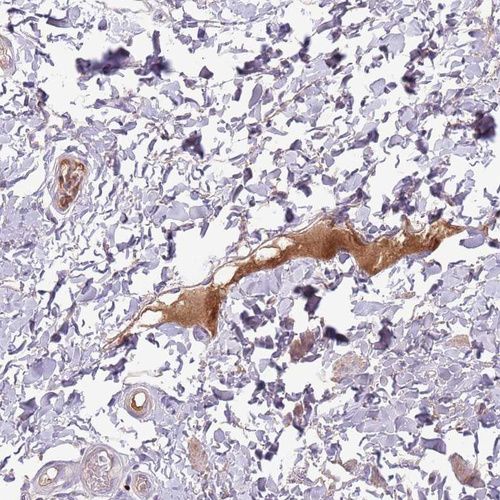

Immunohistochemical staining of human rectum shows strong positivity in plasma.